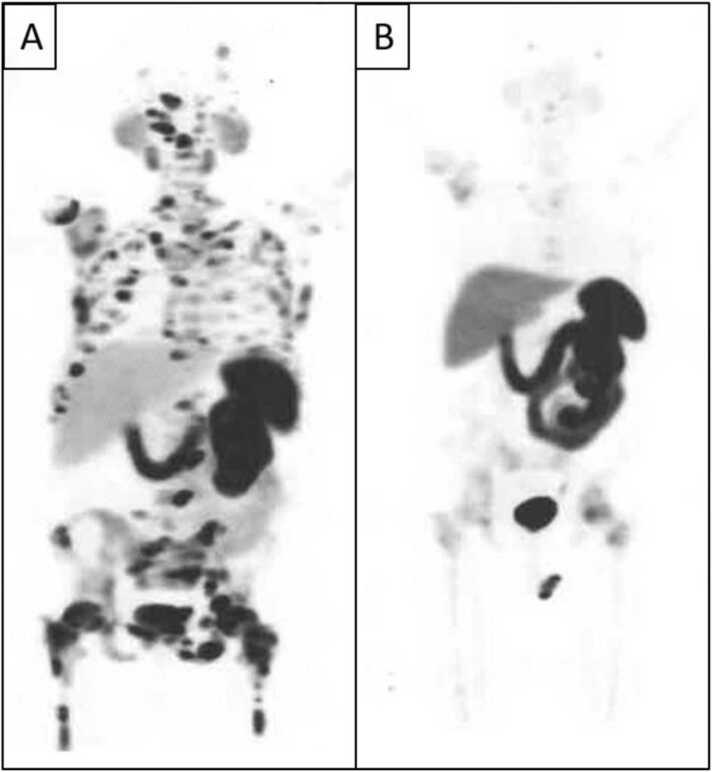

As new molecular tracers are identified to target specific receptors, tissue, and tumor types, opportunities arise for the development of both diagnostic tracers and their therapeutic counterparts, termed "theranostics." While diagnostic tracers utilize positron emitters or gamma-emitting radionuclides, their theranostic counterparts are typically bound to beta and alpha emitters, which can deliver specific and localized radiation to targets with minimal collateral damage to uninvolved surrounding structures. This is an exciting time in molecular imaging and therapy and a step towards personalized and precise medicine in which patients who were either without treatment options or not candidates for other therapies now have expanded options, with tangible data showing improved outcomes. This manuscript explores the current state of theranostics, providing background, treatment specifics, and toxicities, and discusses future potential trends.

随着新的分子示踪剂被确定用于靶向特定受体、组织和肿瘤类型,开发诊断示踪剂及其治疗对应物(即“治疗诊断剂”)的机会应运而生。诊断示踪剂利用正电子发射体或γ发射放射性核素,而它们的治疗诊断对应物通常与β和α发射体结合,这可以将特定的局部辐射传递到靶点,同时对未受影响的周围结构造成最小的附带损伤。这是分子成像和治疗领域令人兴奋的时期,也是迈向个性化精准医学的一步,在这种医学模式下,那些原本没有治疗选择或不适合其他疗法的患者现在有了更多选择,切实的数据表明治疗效果有所改善。本文探讨了治疗诊断学的现状,提供了背景、治疗细节和毒性,并讨论了未来的潜在趋势。